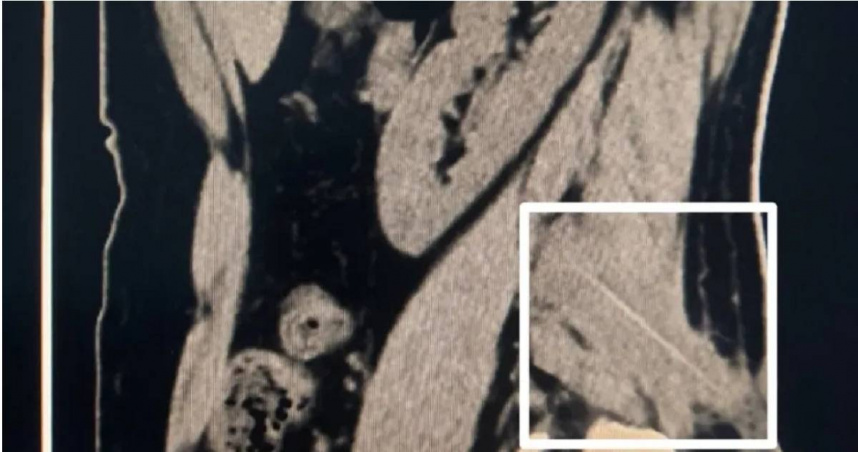

大陸湖南長沙一名48歲男子腰痛,看病半年都沒好轉,到醫院照X光才發現1根牙籤扎進他肉裡,他才想起自己某次喝醉叼著牙籤睡覺,才會渾然不自知。(圖/翻攝自微博)

綜合陸媒報導,湖南省胸科醫院名醫姚其能分享一起病例,來自長沙一名48歲李姓男子他因長期腰痛,到處求醫過了半年都不見好轉,懷疑自己罹患腰大肌膿瘍,才決定到大醫院檢查。姚其能醫師替李男安排核磁共振和趙X光,在多重精密檢查後,在李男的腰部肌肉發現1根長約6公分的異物,最終確認是竹質牙籤殘留。

在找到李男腰部疼痛的原因後,因為牙籤已經在深層肌群裡,要拿出不是一件容易的事情,在該院外科醫師帶領團隊聯合放射科、麻醉手術科等,進行手術,最終將牙籤成功取出。